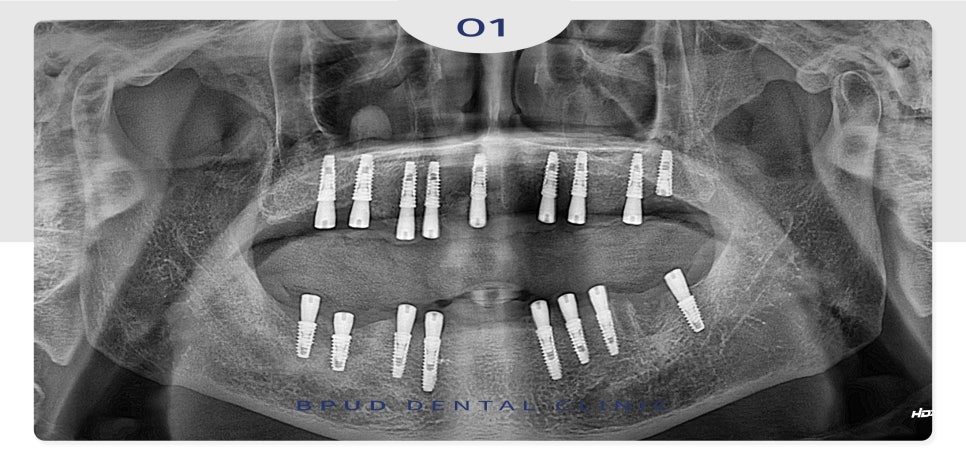

가장 안쪽까지 완성하시길 희망하시며

비용은 줄일 수 있는 방법을

원하신다고 말씀해 주셨는데요.

자연치와 동일하게 위, 아래 각각 14개씩

28개 치아를 제작하기로 하고

양쪽 위쪽은 잇몸뼈가 부족한 부위

상악동을 들어 올려 치조골 이식을 진행하는

상악동거상술을 동반하여

임플란트는 각각 9개, 8개를 식립하였습니다.

하루에 위, 아래 모두 식립을 원하셨으나

환.자분의 연세를 고려하여 하루 간격으로

아래쪽도 잇몸뼈가 부족한 부분은

뼈이식을 동반한 식립을 진행하였습니다.